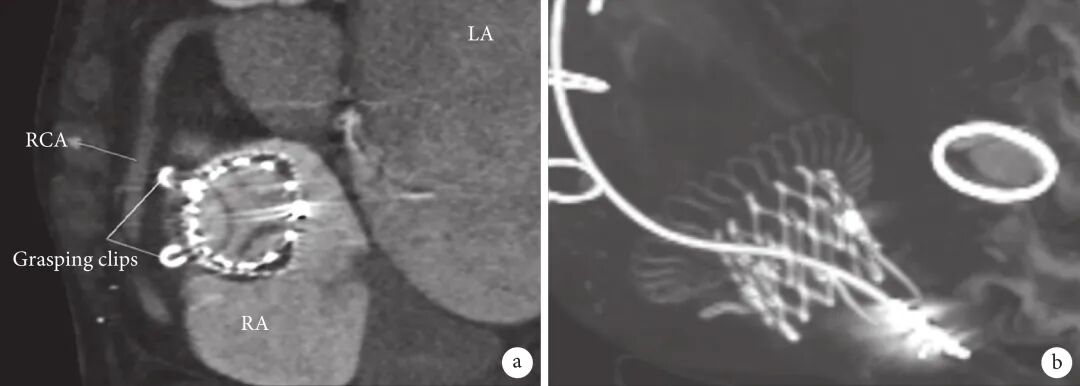

所有患者术后TR 程度均降至≤2+级,4.7%患者残余轻度TR。两组患者在院死亡率分别为10.3%和1.9%,差异有统计学意义(P=0.047)。术后即刻(P=0.270)与术后1个月随访(P=0.483)瓣周漏发生率差异无统计学意义,且在之后的随访中瓣周漏发生率逐渐下降。CIED 组患者TTVR术后CT复查可见人工瓣膜在位,原有起搏导线无挤压、扭曲、偏移等情况;见图1。CIED组与非CIED组心功能改善情况差异无统计学意义(P=0.254)。术后随访1年(P=0.471)和2 年(P=0.426)死亡率差异也无统计学意义。

图 1     CIED组患者TTVR术后复查CT图像

a:CT提示瓣膜在位,前瓣夹持键清晰;b:CT提示瓣膜位置良好,原有起搏导线未见明显扭曲、挤压;CIED:植入式心脏电子装置;TR:三尖瓣反流;TTVR:经导管三尖瓣置换术;LA:左心房;RA:右心房;RCA:右冠状动脉